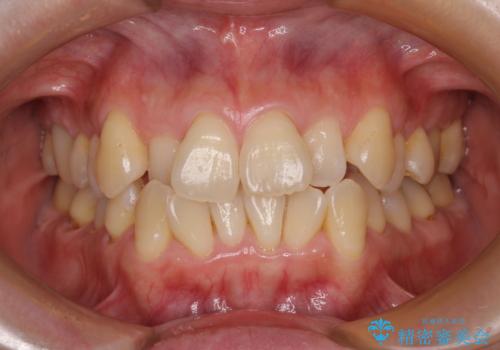

八重歯と開咬の抜歯矯正 ワイヤー装置を併用したインビザライン矯正治療

- 咬み合わない前歯と八重歯などのデコボコを気にして来院された患者様です。

上下前歯の位置を比較すると上顎が前方にあり、デコボコ改善でより上顎が前方に行く可能性があります。

開咬の改善にはインビザラインが有効であり、インビザライン単体での治療を検討しましたが、上顎前突を回避するために上顎左側第一小臼歯抜歯を行うこととしたため、補助装置とワイヤー矯正を併用した上で、インビザラインによる矯正治療を行うこととしました。